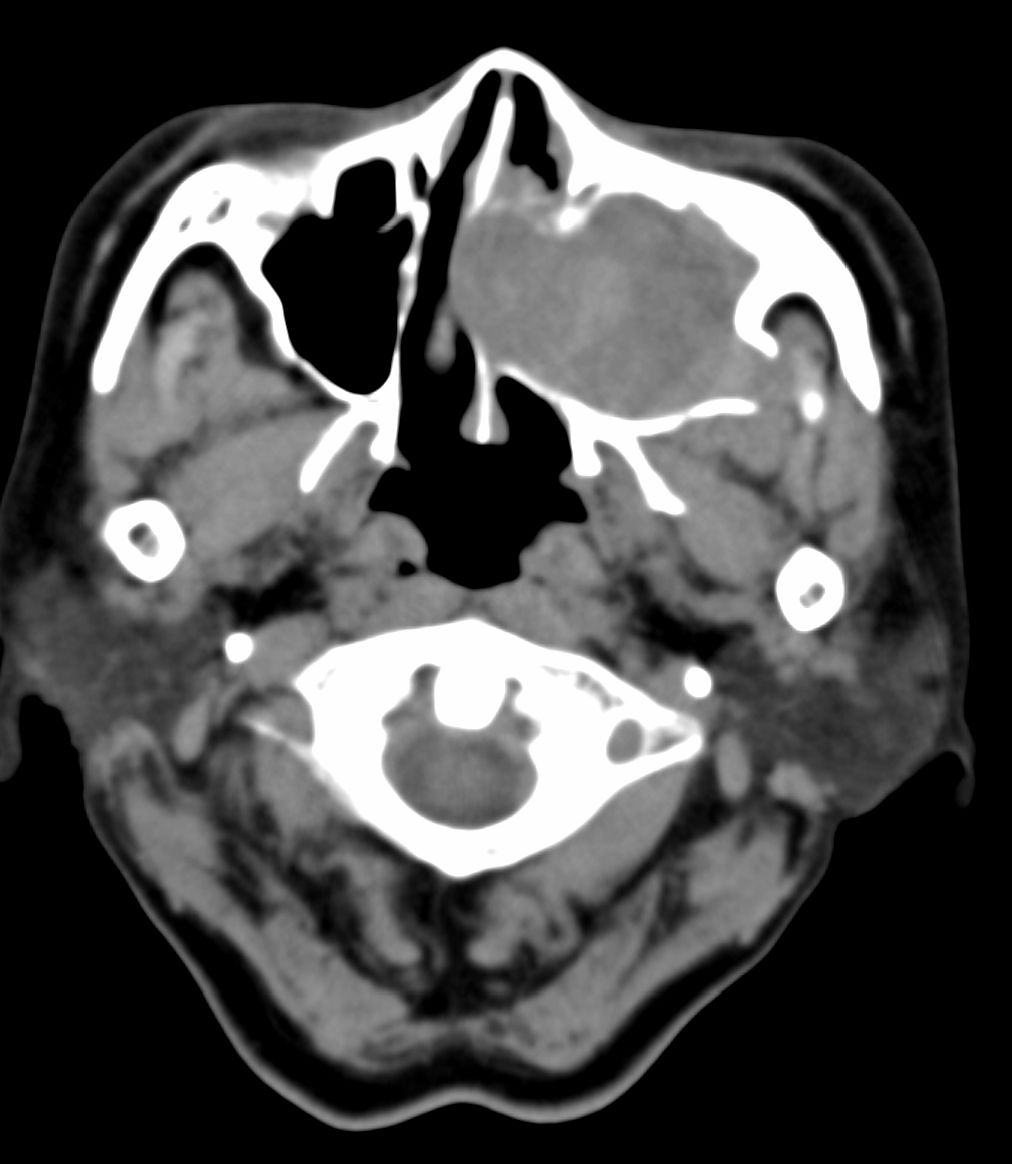

女,69岁。鼻出血2月多。(会诊病史就这样简单)鼻副窦ct检查如下:

左侧鼻腔及上颌窦见软组织块影,左侧上颌窦腔扩大,骨质吸收,右侧上颌窦见半圆形软组织密度影,鼻中隔向右侧弯曲,左侧鼻和鼻窦内翻型乳头状瘤可能性大,建议增强。

左侧上颌窦及鼻腔内见软组织密度影,其内密度不均匀,见斑片状高密度影,右侧上颌窦腔明显扩大,窦壁吸收变薄,鼻中隔右偏,右侧上颌窦见一半圆形软组织密度影,边界清楚,其内密度均匀。诊断,1、左侧鼻腔及上颌窦内翻乳头状瘤可能性大,上颌窦癌,息肉及霉菌性上颌窦炎待除外。2、右侧上颌窦粘膜下囊肿。

1)考虑左侧上颌窦内翻乳突状瘤突入左侧鼻腔。2)副鼻窦炎,右侧上颌窦黏膜下囊肿。

病理:霉菌性左侧上颌窦炎伴左侧上颌窦纤维组织增生。

窦腔密度不均匀增高,无明显钙化征象,后外侧及内侧窦壁膨胀明显,局部破坏消失,筛窦受累及,但双侧对比发现左侧窦壁骨质有硬化增白现象,这可能是支持左侧霉菌性上颌窦炎的主要依据点。